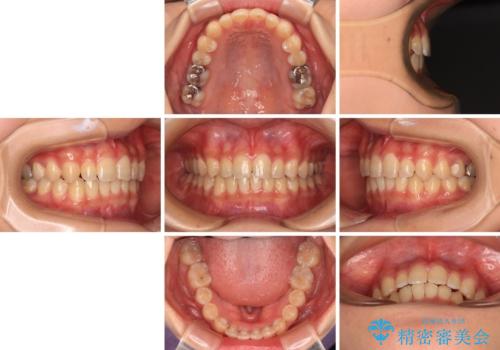

深い咬み合わせとデコボコの歯列をワイヤー矯正で改善

- 前歯のデコボコと深い咬み合わせを改善したいとのことで来院された患者様です。

奥歯の咬み合わせは上顎に対して下顎が後方位にあり、上顎前歯で下顎前歯が隠れるような典型的な過蓋咬合です。

補助装置を用いて上顎大臼歯を後方に移動させながら、ワイヤー装置で歯列を整えて深い咬み合わせを挙上することとしました。